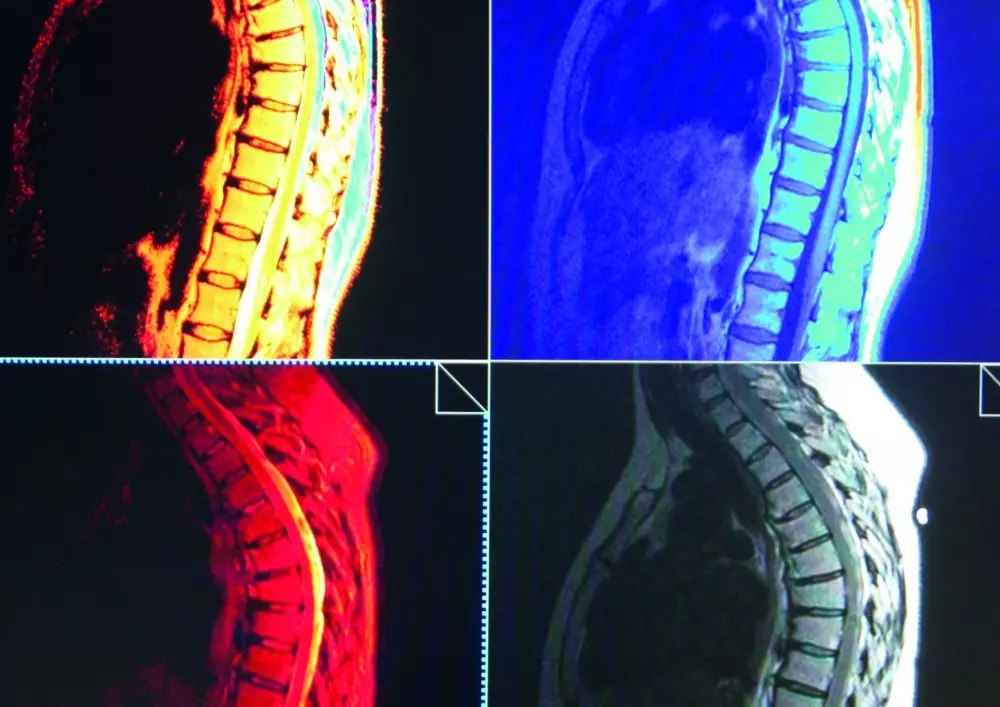

- diagnostyka różnicowa odcinka piersiowego kręgosłupa i klatki piersiowej

Na łamach naszego czasopisma ponownie pojawia się diagnostyka różnicowa, tym razem w przypadku odcinka piersiowego kręgosłupa i klatki piersiowej. Zachęcamy do zapoznania się z artykułem autorstwa Piotra Godka.